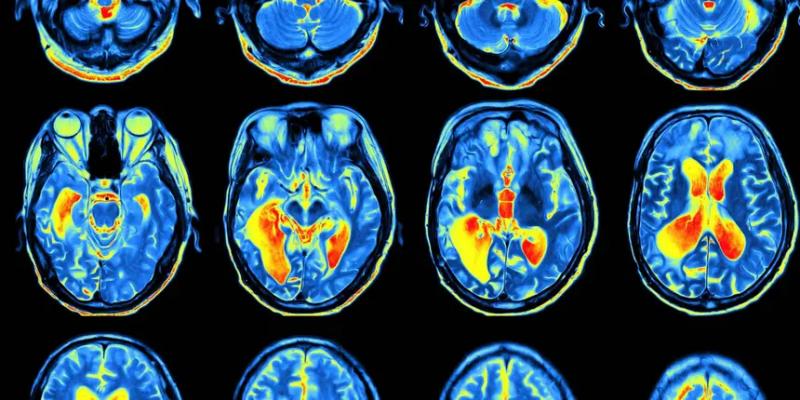

Чтобы понять, как мозг отличает реальность от вымысла, учёные показывали участникам эксперимента трудноразличимые узоры и одновременно проводили сканирование их мозга. Люди смотрели на экран со статическим фоном, на котором иногда был наложен едва заметный узор из диагональных полос. Эти полосы могли быть наклонены как вправо, так и влево.

При помощи функциональной магнитно-резонансной томографии (фМРТ) мозга была выявлена более активная область, когда участники сообщали, что видели какой-то рисунок. Эта веретенообразная извилина находится в районе висков. Она активируется как при виде чего-то в реальности, так и при представлении этого. Интересно, что эта активация предсказывает, считаем ли мы что-либо реальным. Далее этот сигнал оценивается передней островковой долей. Активность выше определённого порога воспринимается как реальная, а активность ниже — как воображаемая.